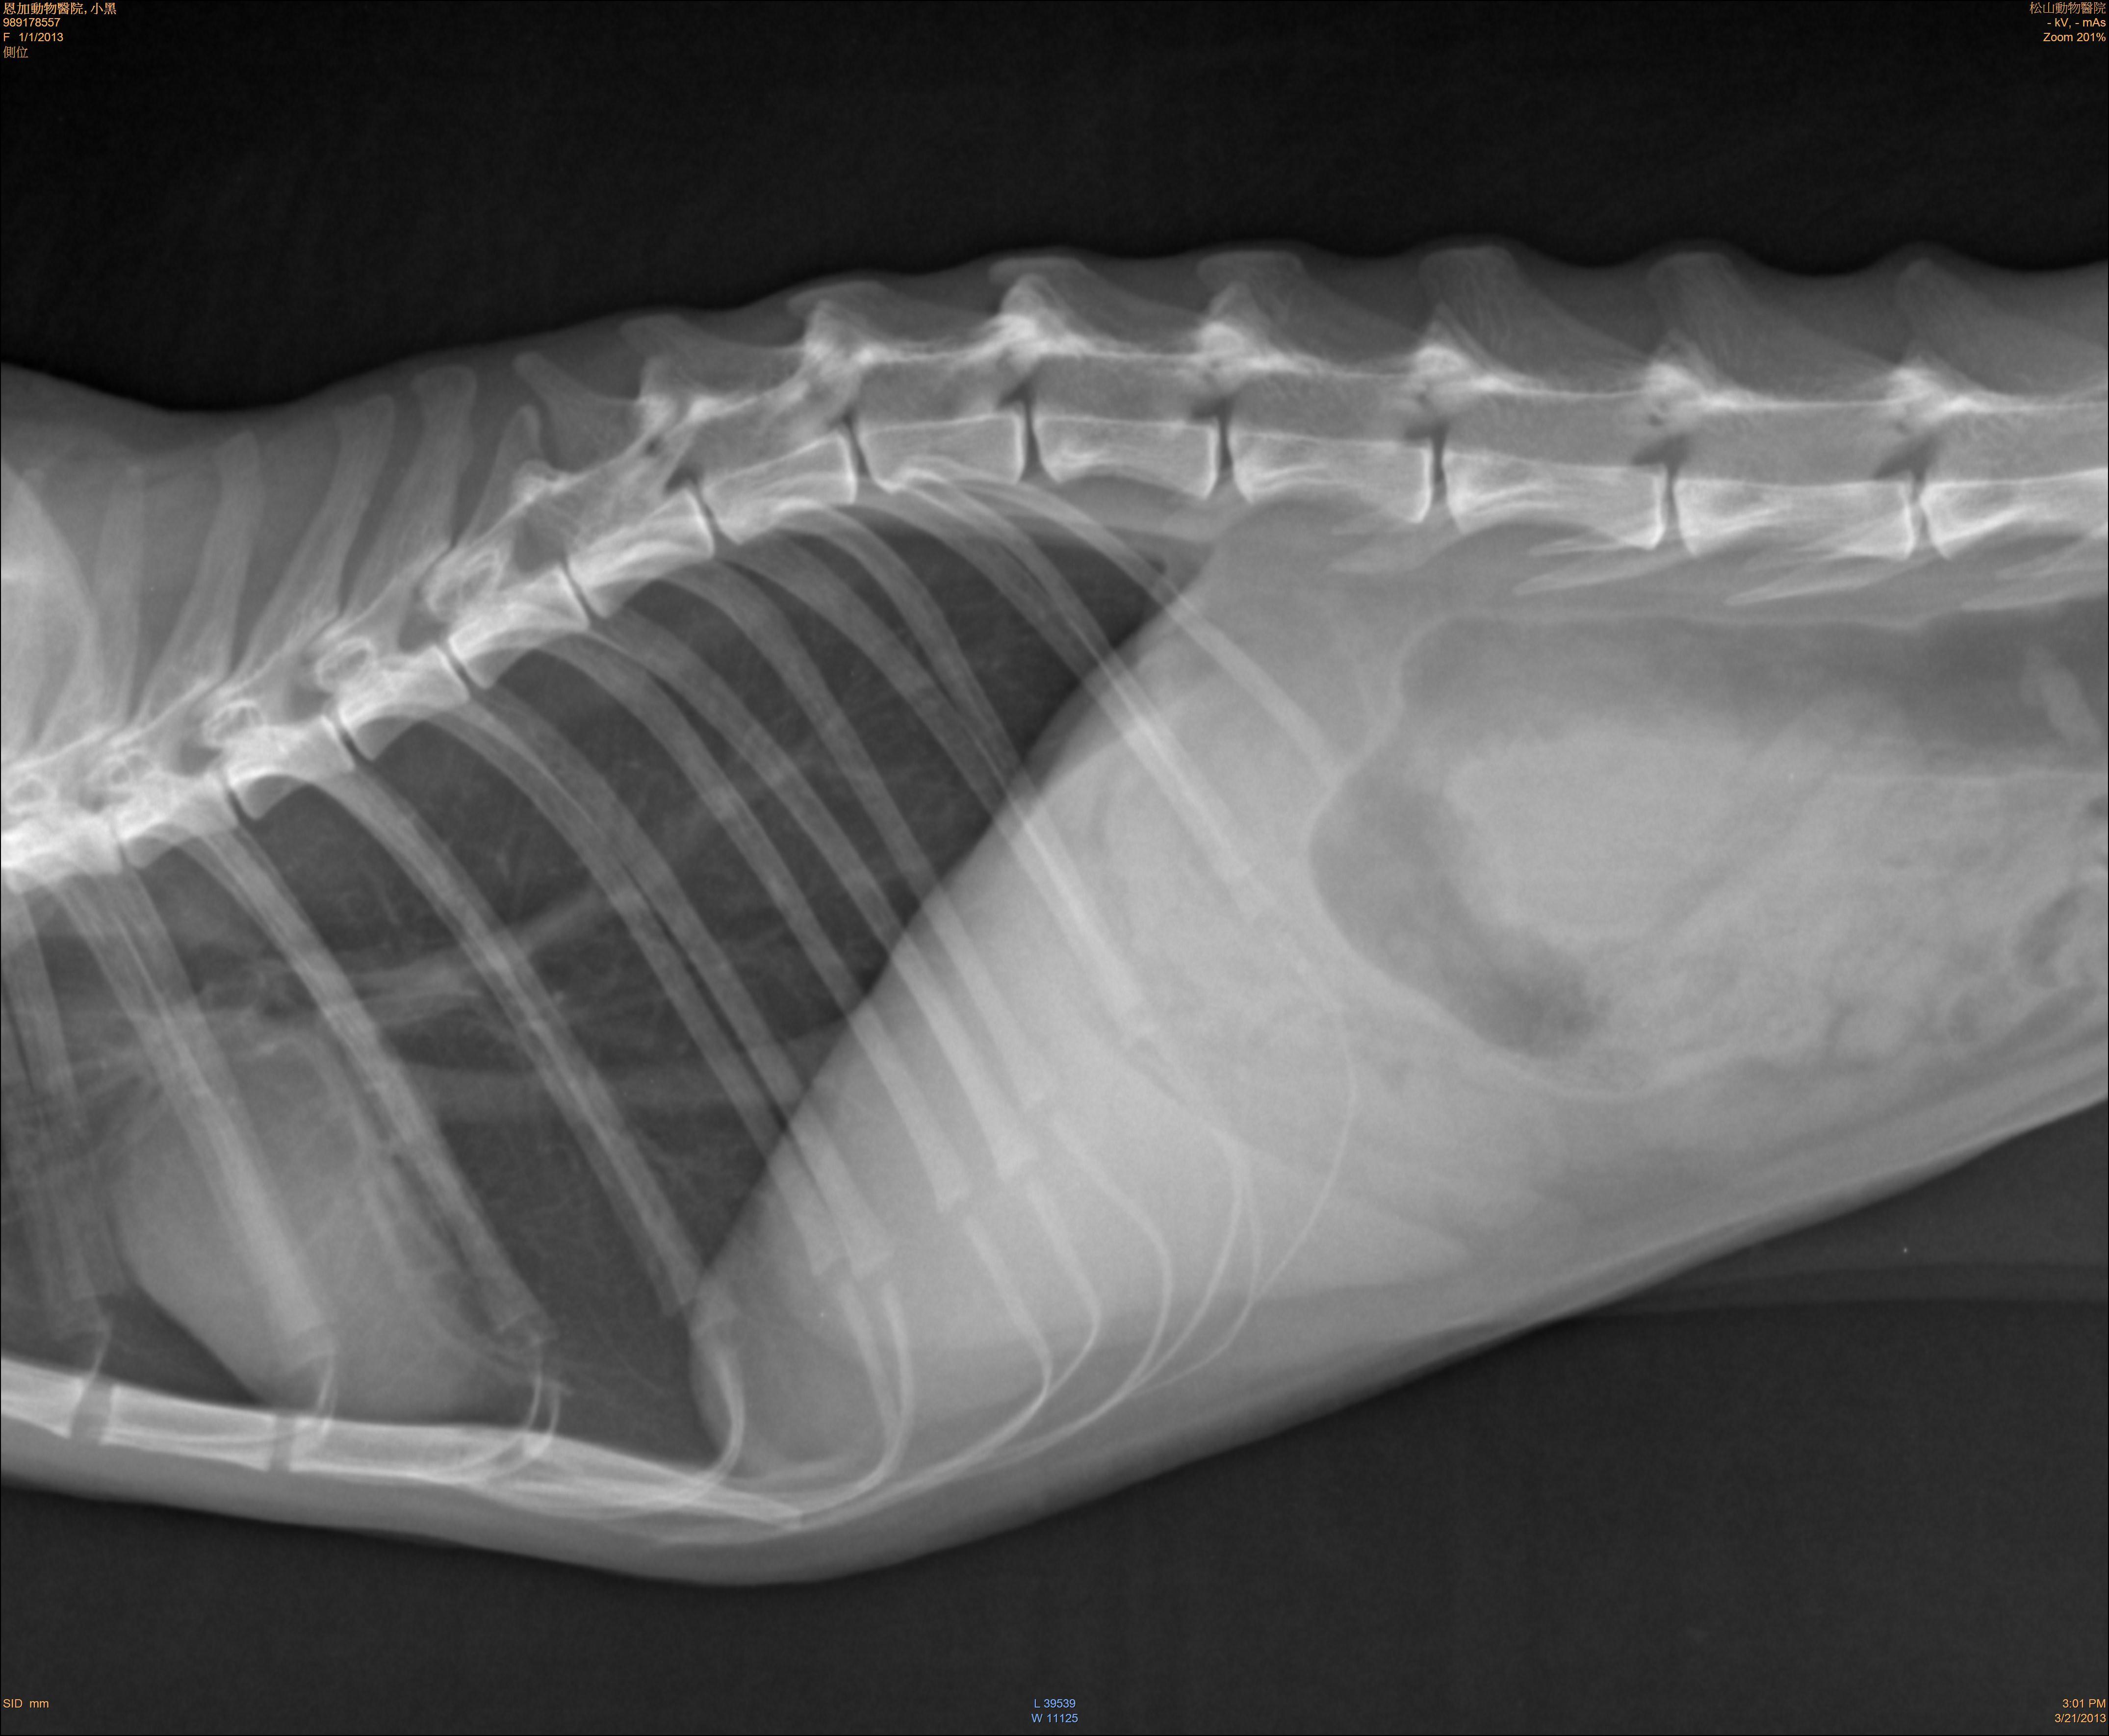

主題: 消瘦不吃虎斑貓 申請者姓名: 張慧敏 花色: 申請日期: 2013-05-08 18:09:34 申請者部落格: 申請者臉書網址: 所在縣市/合作醫院: 台北市/恩加動物醫院 治療費用: 14400元 需求人數: 32人 已結案 (2013-08-06 14:17:12) 報名人員: alicelin x4(已付款)、Amanda Lo x2(已付款)、Linda(已付款)、Chloe Liang(已付款)、Nico Huang(已付款)、treaci(已付款)、林雅雯(已付款)、lavinia x2(已付款)、Ray Lei(已付款)、Emily Chou x10(已付款)、Rebecca Wu(已付款)、Lulu Hsieh(已付款)、假不妙(已付款)、Winnie Chou(已付款)、Antelie(已付款)、Page Chang(已付款)、簡楓峻、簡楓峻、kid x2(已付款)、 候補人員: 動物病情說明: 在新北市平溪區山上餵養的浪貓,發現體型消瘦不吃東西,精神不佳,送醫治療,經過多項血液生化檢查、X光檢查,點滴治療,仍然回天乏術。